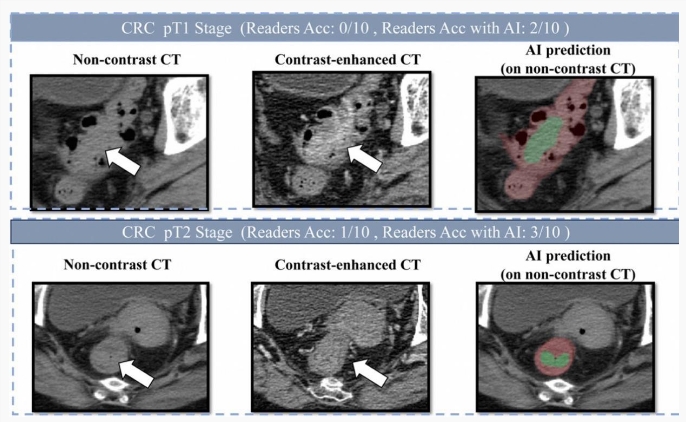

为克服肠道内容物对影像的干扰,达摩院的技术团队采用了 “先定位、后诊断” 的深度学习架构,并专门针对小于 3 厘米的早期肿瘤进行训练。这种两阶段的学习策略,使得 AI 模型能够有效地分割复杂的肠道区域,从而更准确地检测出可疑病灶。